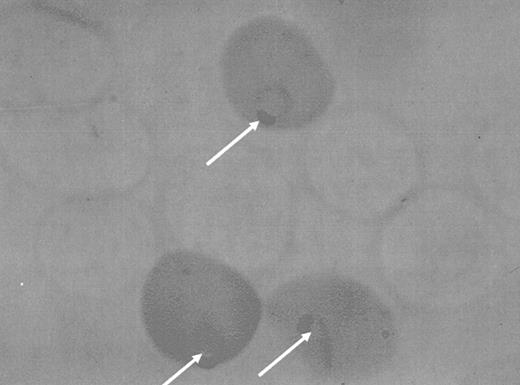

But what was the defect that led to primaquine sensitivity? The fact that younger, metabolically more active red cells resisted the assault of the drug suggested the possibility that primaquine-sensitive cells had an intrinsic metabolic defect. There were few morphologic changes in the red cells of subjects undergoing primaquine-induced hemolysis, but Heinz bodies could be detected in the circulation before the onset of hemolysis. Heinz bodies can be induced in vitro by compounds such as phenylhydrazine or acetyl phenylhydrazine, and we were able to show that the pattern of in vitro Heinz body formation was quite different in sensitive and nonsensitive subjects (Figure 2).12 This made it possible, for the first time, to detect primaquine sensitivity in vitro. More important, it provided a system in which metabolic inhibitors could be used to attempt to simulate primaquine sensitivity in vitro. The fact that iodoacetate and arsenite caused normal cells to behave like primaquine-sensitive cells13 focused attention on the sulfhydryl groups of the erythrocyte. The amount of glutathione in the cells13 was diminished, and the ability of erythrocytes to maintain glutathione levels in the face of an oxidative stress14,15 was abnormal. Carson et al3 then undertook a study of the reduction of glutathione by hemolysates. Fifty years ago nicotinamide adenine dinucleotide phosphate (NADPH; then known as TPNH) was very costly, and therefore an attempt was made to generate the reduced coenzyme in hemolysates from NADP and glucose-6-P through the G6PD reaction. When it was found that hemolysates from primaquine-sensitive men could not utilize glucose-6-phosphate to reduce glutathione, the more expensive NADPH was added as the hydrogen donor. This substrate could reduce glutathione in hemolysates from primaquine-sensitive men, making it apparent that the primary defect was in the glucose-6-P-utilizing enzyme, G6PD.

The Heinz body test for primaquine sensitivity (G6PD deficiency). The cells (right) are from a primaquine-sensitive (G6PD-deficient) donor; the cells in the left panel, from a normal control.